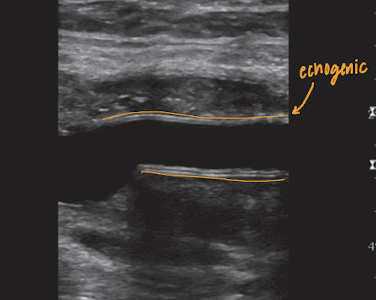

(prosthetic) PTFE grafts have a distinctive…

double line appearance of graft wall